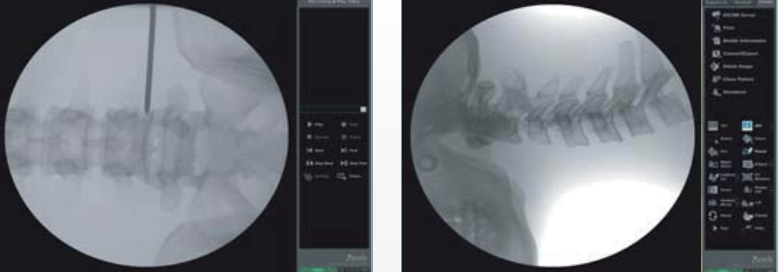

척추 신경주사치료는 통증을 유발하는 척추 신경 주변에 직접 약물을 주입하여 염증을 가라앉히고, 과민해진 신경을 안정시켜 통증을 완화하는 정밀한 시술입니다. 실시간 영상 장치(C-arm)를 보면서 병변 부위를 정확하게 확인하고 치료하므로 안전하고 효과가 빠릅니다.

3. 통증유발신경 확인

4. C-arm 주사 삽입과 약물주입